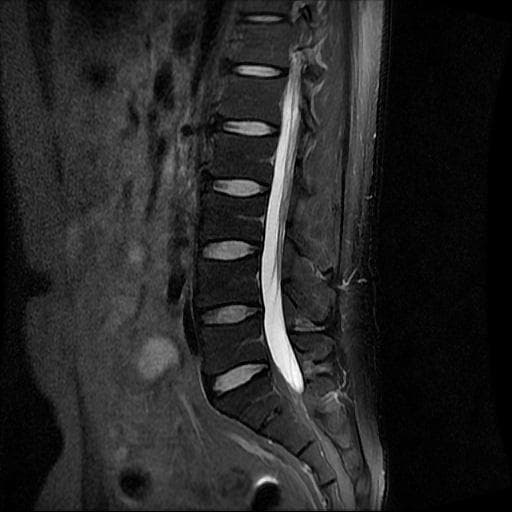

허리 MRI 디스크 상태 분석 부탁드립니다

건협에서는 관리해야 된다는데 디스크 협착이나 팽윤 등이 있는 상태인지 궁금합니다.

우선 현재로썬 사진만으론 판단을 하기에 제한이 되지만 사진상 디스크 상태는 심해보이지 않습니다.

요추부위의 하부 에서 약간의 팽윤이나 돌출로 의심해볼수 있는 정도이지만, 정확한 상태는 관련 전문의에게 진료시 문의를 하시는 것을 추천드립니다.